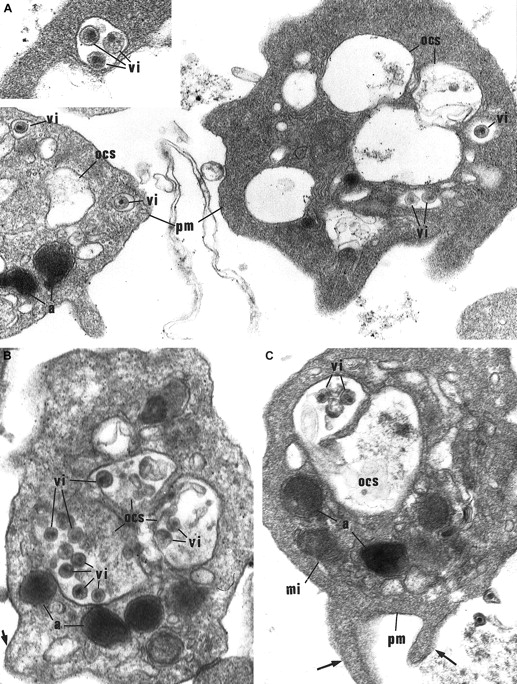

Morphological study of washed platelets incubated with HIV particles.

(A) Internalization of HIV particles in endosomelike structures. In the early stage of internalization, HIV particles are found in some characteristic small vacuoles as endosomelike structures tightly surrounding 1 or 2 particles (vi), and located close to the plasma membrane (pm). a indicates α-granules. Original magnification, × 36 800; inset original magnification, × 55 200. (B) (C) HIV particles (vi) are further retrieved in the OCS. These platelets show morphological activation signs: spherical shape, bristled surface with pseudopods (arrows), dilated OCS. mi indicates mitochondria. Original magnification, × 41 850.

HIV internalization occurs preferentially in activated platelets.

Interestingly, viral particles were observed exclusively in platelets undergoing secretion and displaying morphological activation signs: uneven surface, extension of pseudopods, degranulation, and dilated OCS (Figure 4A-C).